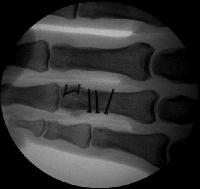

Xrays show a complex intraarticular fracture of the proximal phalanx head. There is a displaced spiral oblique longitudinal fracture with a second oblique coronal split through the articular surface of the radial condyle.

Intraoperative fluoroscopy.